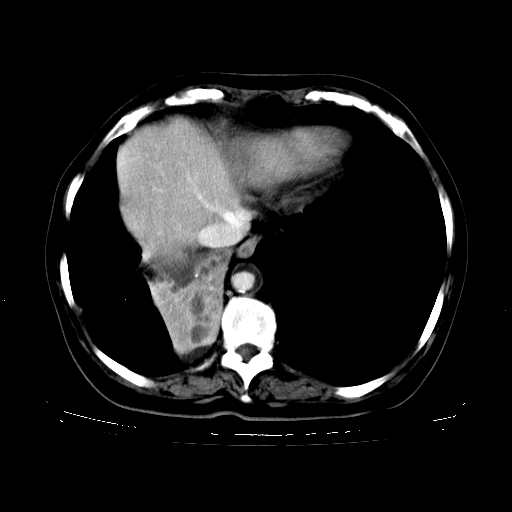

标题: CT23067:女,70岁,咳嗽、咳痰一个月,低热一周。 [打印本页]

女,70岁,咳嗽、咳痰一个月,低热一周。

1、右肺占位,考虑周围型ca 。

2、右下肺软组织密度肿块影,考虑肺隔离征。

3、两肺肺结核(右肺下叶背段及左肺)。

4、主动脉夹层。

5、右侧少量胸腔积液。